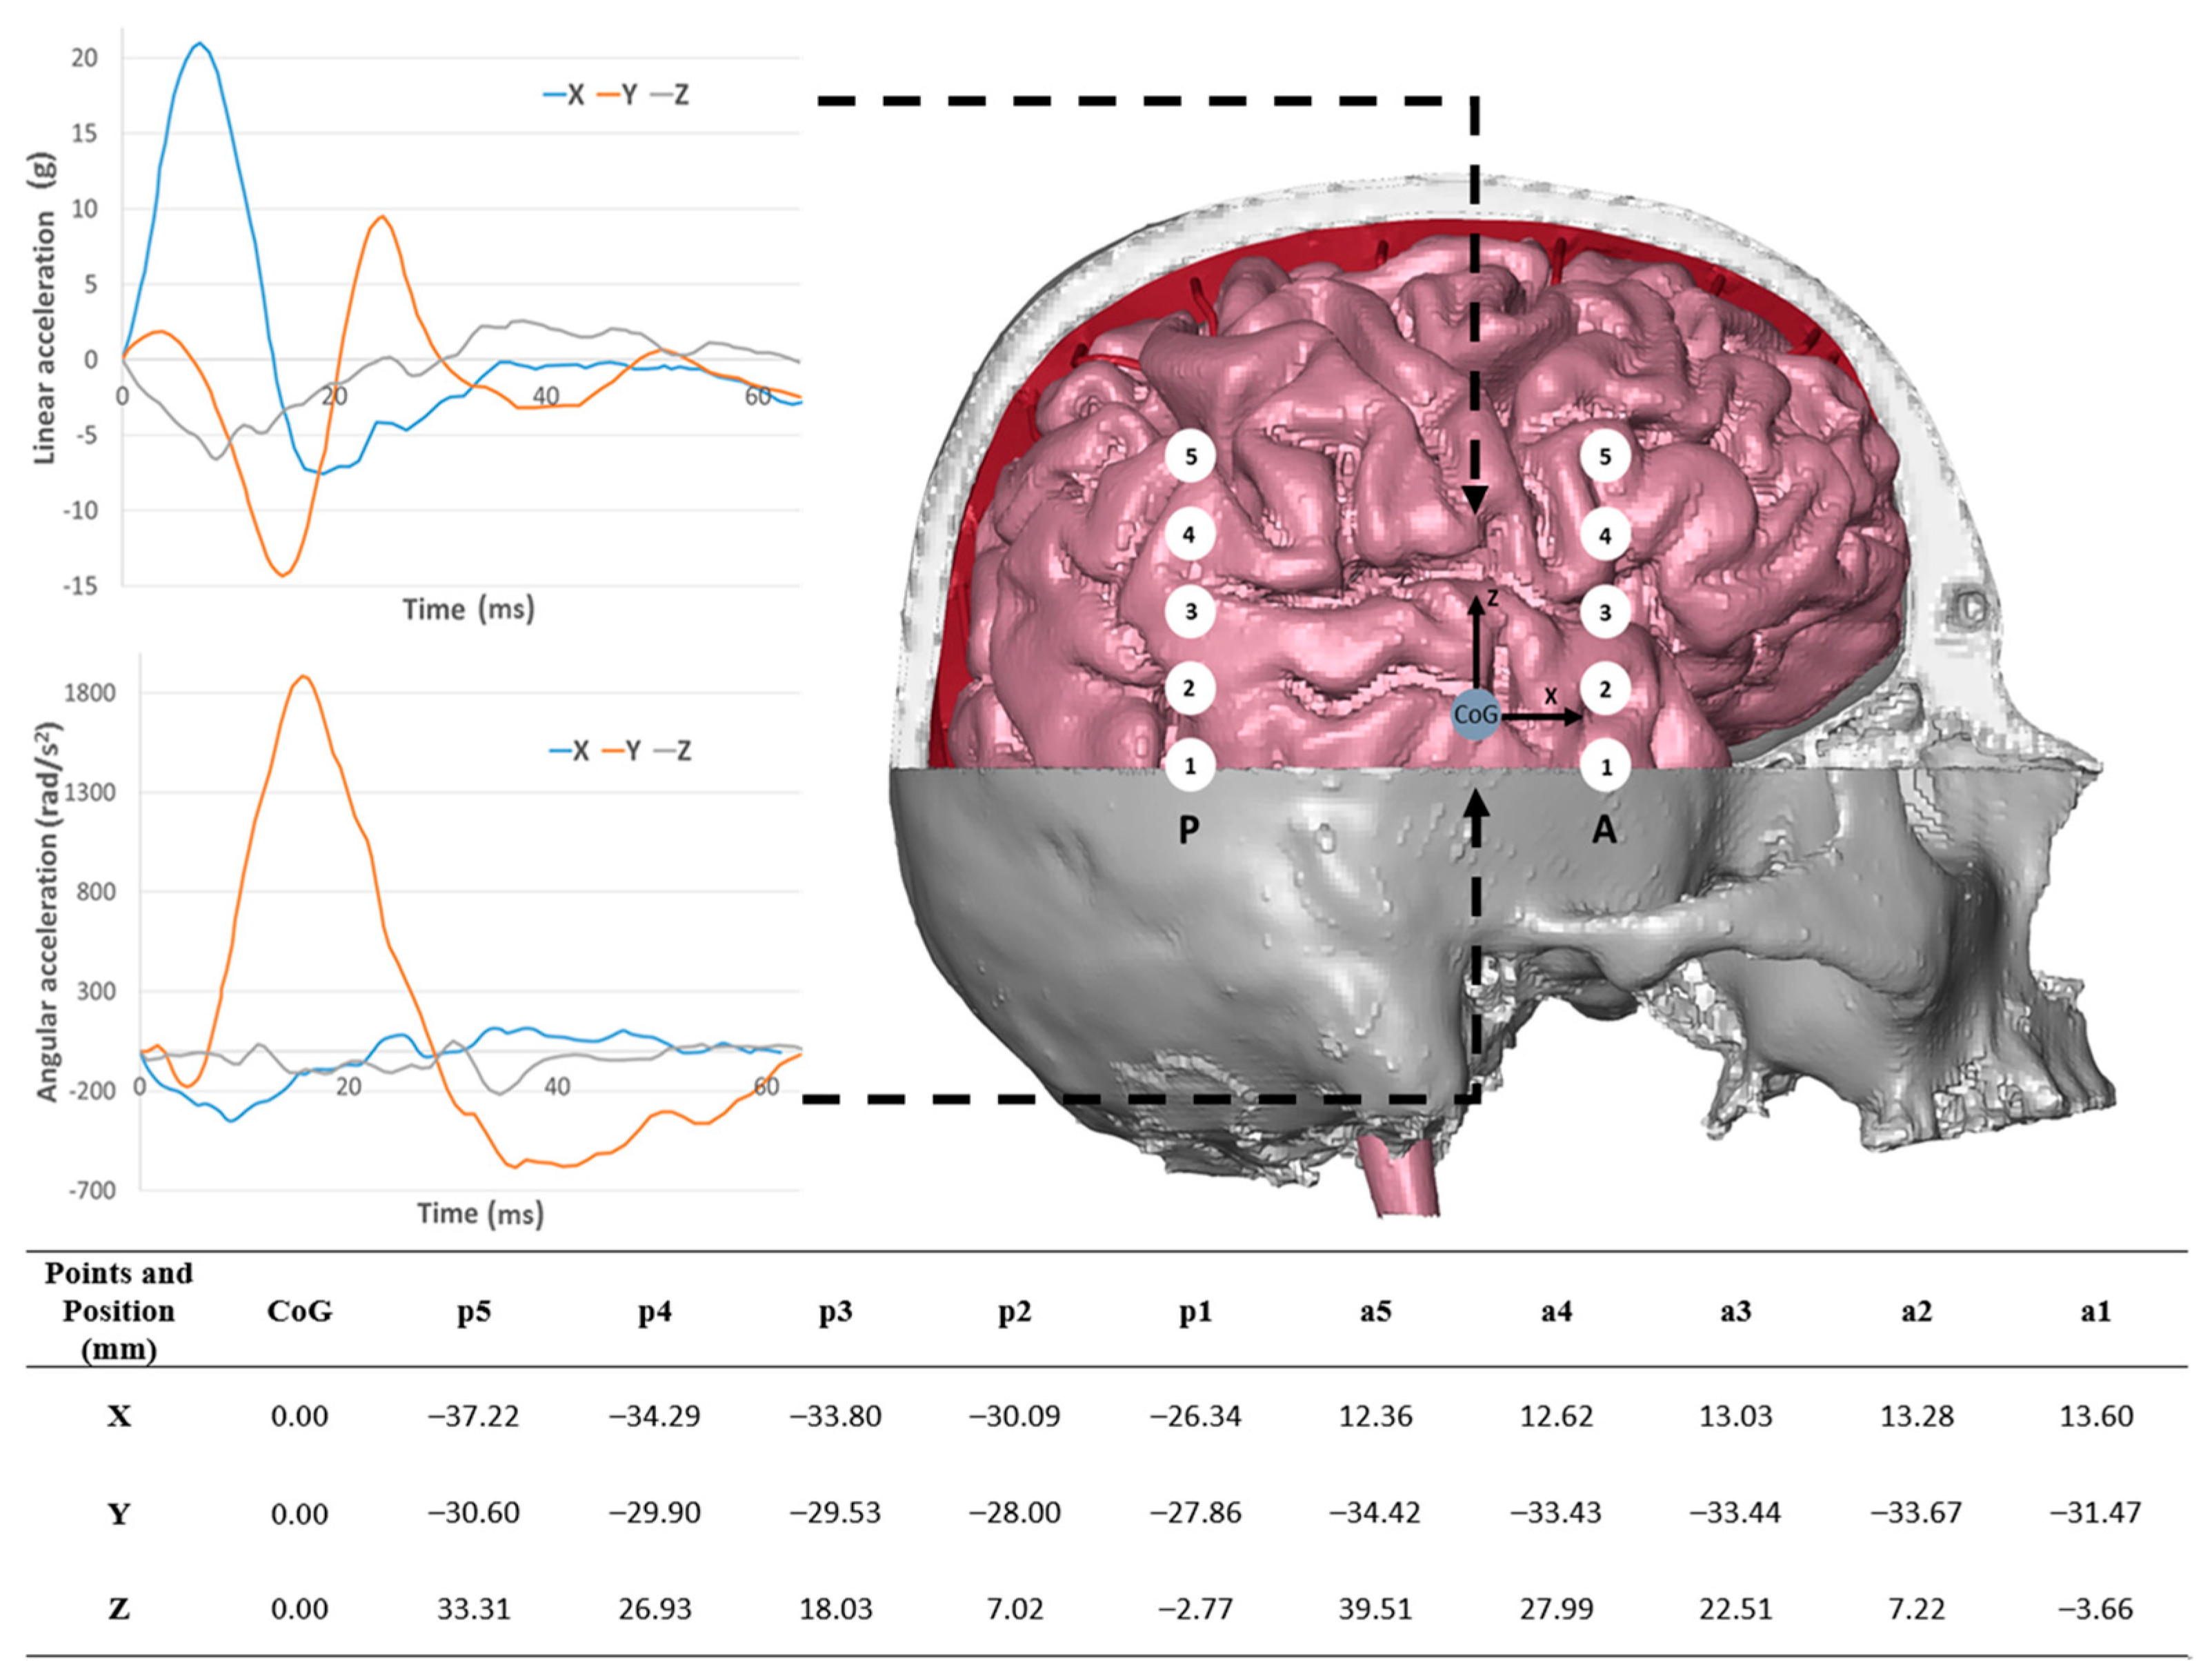

2.1. Case Studies

2.5. Validation Boundary Conditions

3. Results